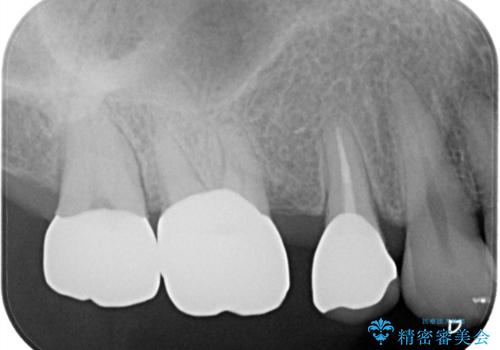

歯間空隙は、患者様と相談した清掃性を考慮し、結果的に残すこととなりました。